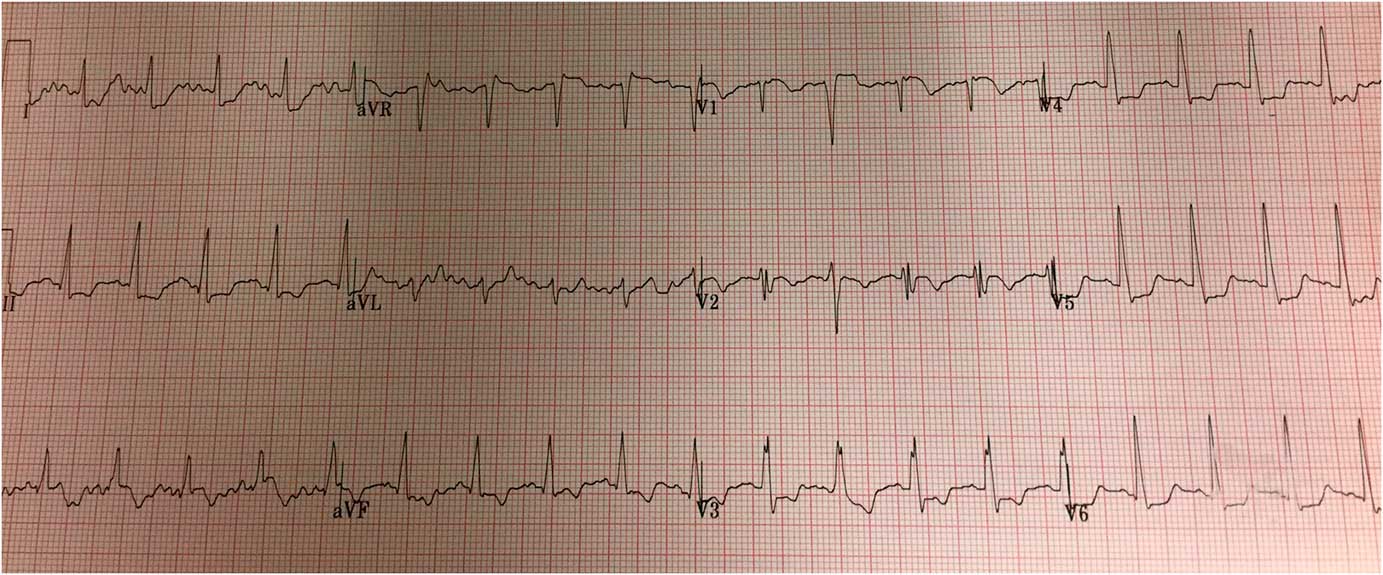

The patient’s clinical condition deteriorated en route, and attending paramedics elected to deliver the patient to the ED instead. Upon arrival at 16:40, the patient was cyanotic, dyspneic, and somnolent. Central pulses were palpable, although non-invasive blood pressure and oxygen saturation were undetectable. The skin of his lower extremities was mottled. Engorged superficial veins were noted across the patient’s abdomen and right flank; examination of the lower extremities revealed clusters of engorged varicose and superficial veins over the medial right thigh. Supplemental oxygen, intravenous (IV) normal saline, and norepinephrine infusion were initiated. His ED ECG showed lateral ST depression, ST elevation in aVR and V1, and an incomplete right bundle branch block pattern (Figure 2). Bedside point-of-care ultrasound (PoCUS), performed in the resuscitation room, revealed a hyperdynamic and partially collapsed left ventricle, dilated right ventricle, and global right ventricular systolic dysfunction (Video 1). A pulmonary embolus (PE) was strongly suspected.

Figure 2 Emergency department 12-lead ECG. Findings include sinus tachycardia, lateral ST depression, ST elevation in aVR and V1, and incomplete RBBB. The QRS duration is 100ms.

3. ECG: precordial T-wave inversion; precordial ST depression; precordial Qr pattern; S1Q3T3; new right bundle branch block; right or indeterminate axis deviation; and ST elevation in aVR.Reference Livaditis, Paraschos and Dimopoulos 11 , Reference Ferrari, Imbert and Chevalier 12

Anterior ST elevation, noted in our patient’s pre-hospital ECG, is uncommon in acute PE, though it has been described.Reference Livaditis, Paraschos and Dimopoulos 11 , Reference Lin, Lin and Yang 15 , Reference Falterman, Martinez, Daberkow and Weiss 16 Proposed mechanisms include right ventricular strain and injury because of increased afterload; rarely, this finding can reflect coronary occlusion due to a clot through a patent foramen ovale.Reference Lin, Lin and Yang 15 , Reference Cheng 17 It is often visually indistinguishable from the ST elevation seen in an acute myocardial infarction; however, the simultaneous (or subsequent) presence of more specific ECG findings may raise the index of suspicion for PE at a patient’s bedside.Reference Lin, Lin and Yang 15 In patients with cardiogenic shock, anterior T-wave inversions and ST elevation in leads aVR and V1 are associated with PE.Reference Ferrari, Imbert and Chevalier 12 , Reference Kukla, McIntyre and Fijorek 18